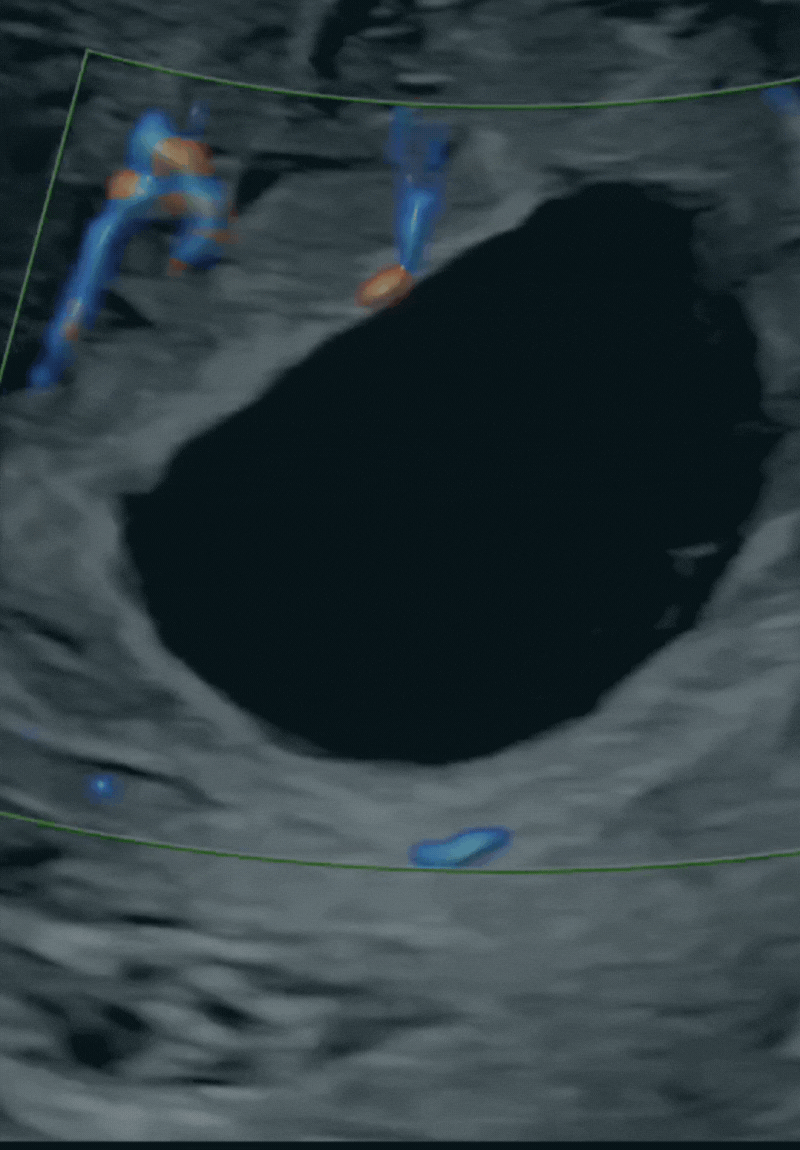

Ecografía Doppler

La Ecografía Doppler evalúa el flujo sanguíneo en los vasos maternos y fetales, es esencial para el seguimiento de posibles problemas de crecimiento de bebé. Esta técnica no invasiva es un pilar en el diagnóstico y seguimiento de embarazos de alto riesgo.